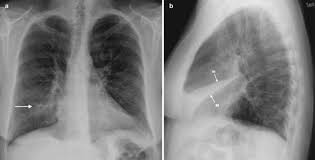

If you do have signs and symptoms, they may include: However, some residual scarring or damage may occur. Weak breathing (respiratory) muscles due to muscular dystrophy, spinal cord injury or another neuromuscular condition 8. Mucus plugs are also common in children, people with cystic fibrosis and during severe asthma attacks. Atelectasis, the collapse of part or all of a lung, is caused by a blockage of the air passages (bronchus or bronchioles) or by pressure on the lung. risk factors for atelectasis include anesthesia, prolonged bed rest with few changes in position, shallow breathing and underlying lung disease.

Recent abdominal or chest surgery 6. Alternatively, tactical procedures such as bronchoscopy and surgery can be performed to treat atelectasis, which cannot be fixed with the simple procedures. Atelectasis in children is often caused by a blockage in the airway. It occurs when the tiny air sacs (alveoli) within the lung become deflated or possibly filled with alveolar fluid. See full list on mayoclinic.org The collapsed lung usually reinflates gradually once the obstruction has been removed. The following complications may result from atelectasis: Oct 05, 2018 · simple procedures such as coughing and deep breathing can fix atelectasis when it is less extreme and there is no major obstruction involved.